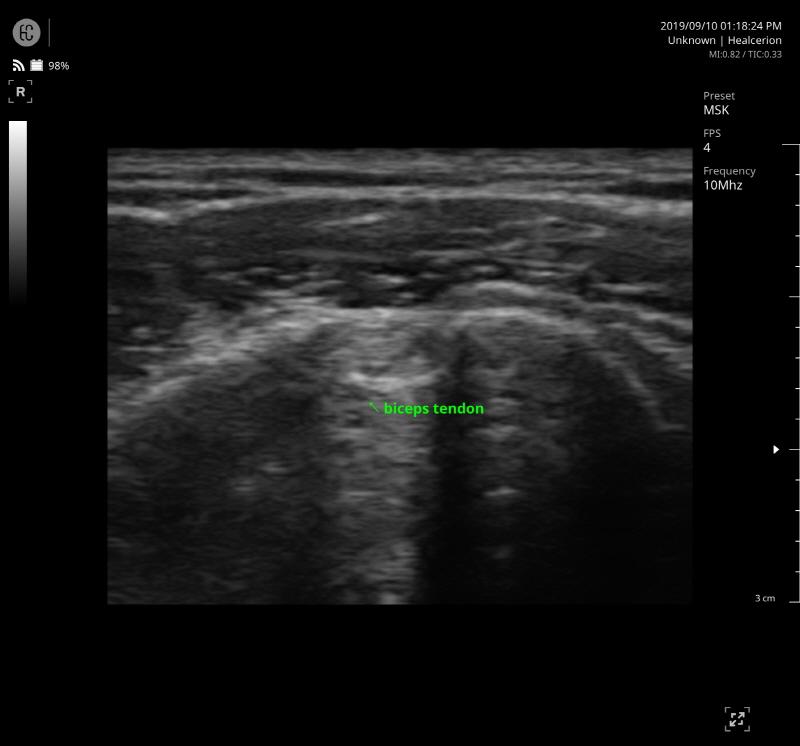

SONON 300L ecografía 1 SONON 300L ecografía 2 SONON 300L ecografía 3